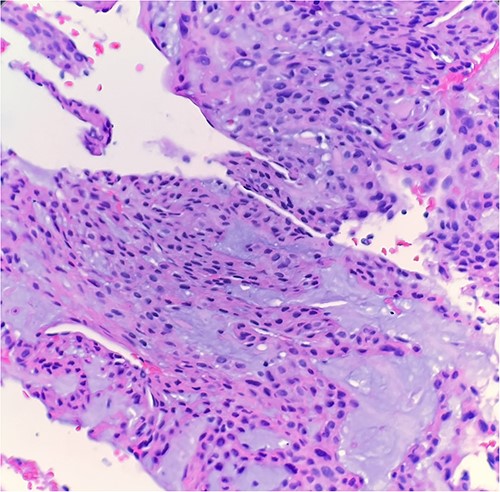

The excised mass was a fragment of tan red soft tissue measuring 0.7 × 0.4 × 0.4 cm. Microscopic examination reveals that tumor is composed of epithelioid bland cells forming gland-like architecture with scant mucinous material (Fig. 1). Without immunohistochemical stain, the morphological features are diagnostic for adenocarcinoma. However, in order to rule out other diagnostic possibility, we performed smooth muscle actin (SMA) immunohistochemical stain. The tumor cells turn out to be positive for SMA (Fig. 2). Combined with this immunoprofile, the final diagnosis of glomus tumor was rendered. The diagnosis of glomus tumor was confirmed with second opinion at world renowned institute.

Microscopic examination reveals epithelioid bland tumor cells forming glandular structure with mucinous material. H&E ×40.